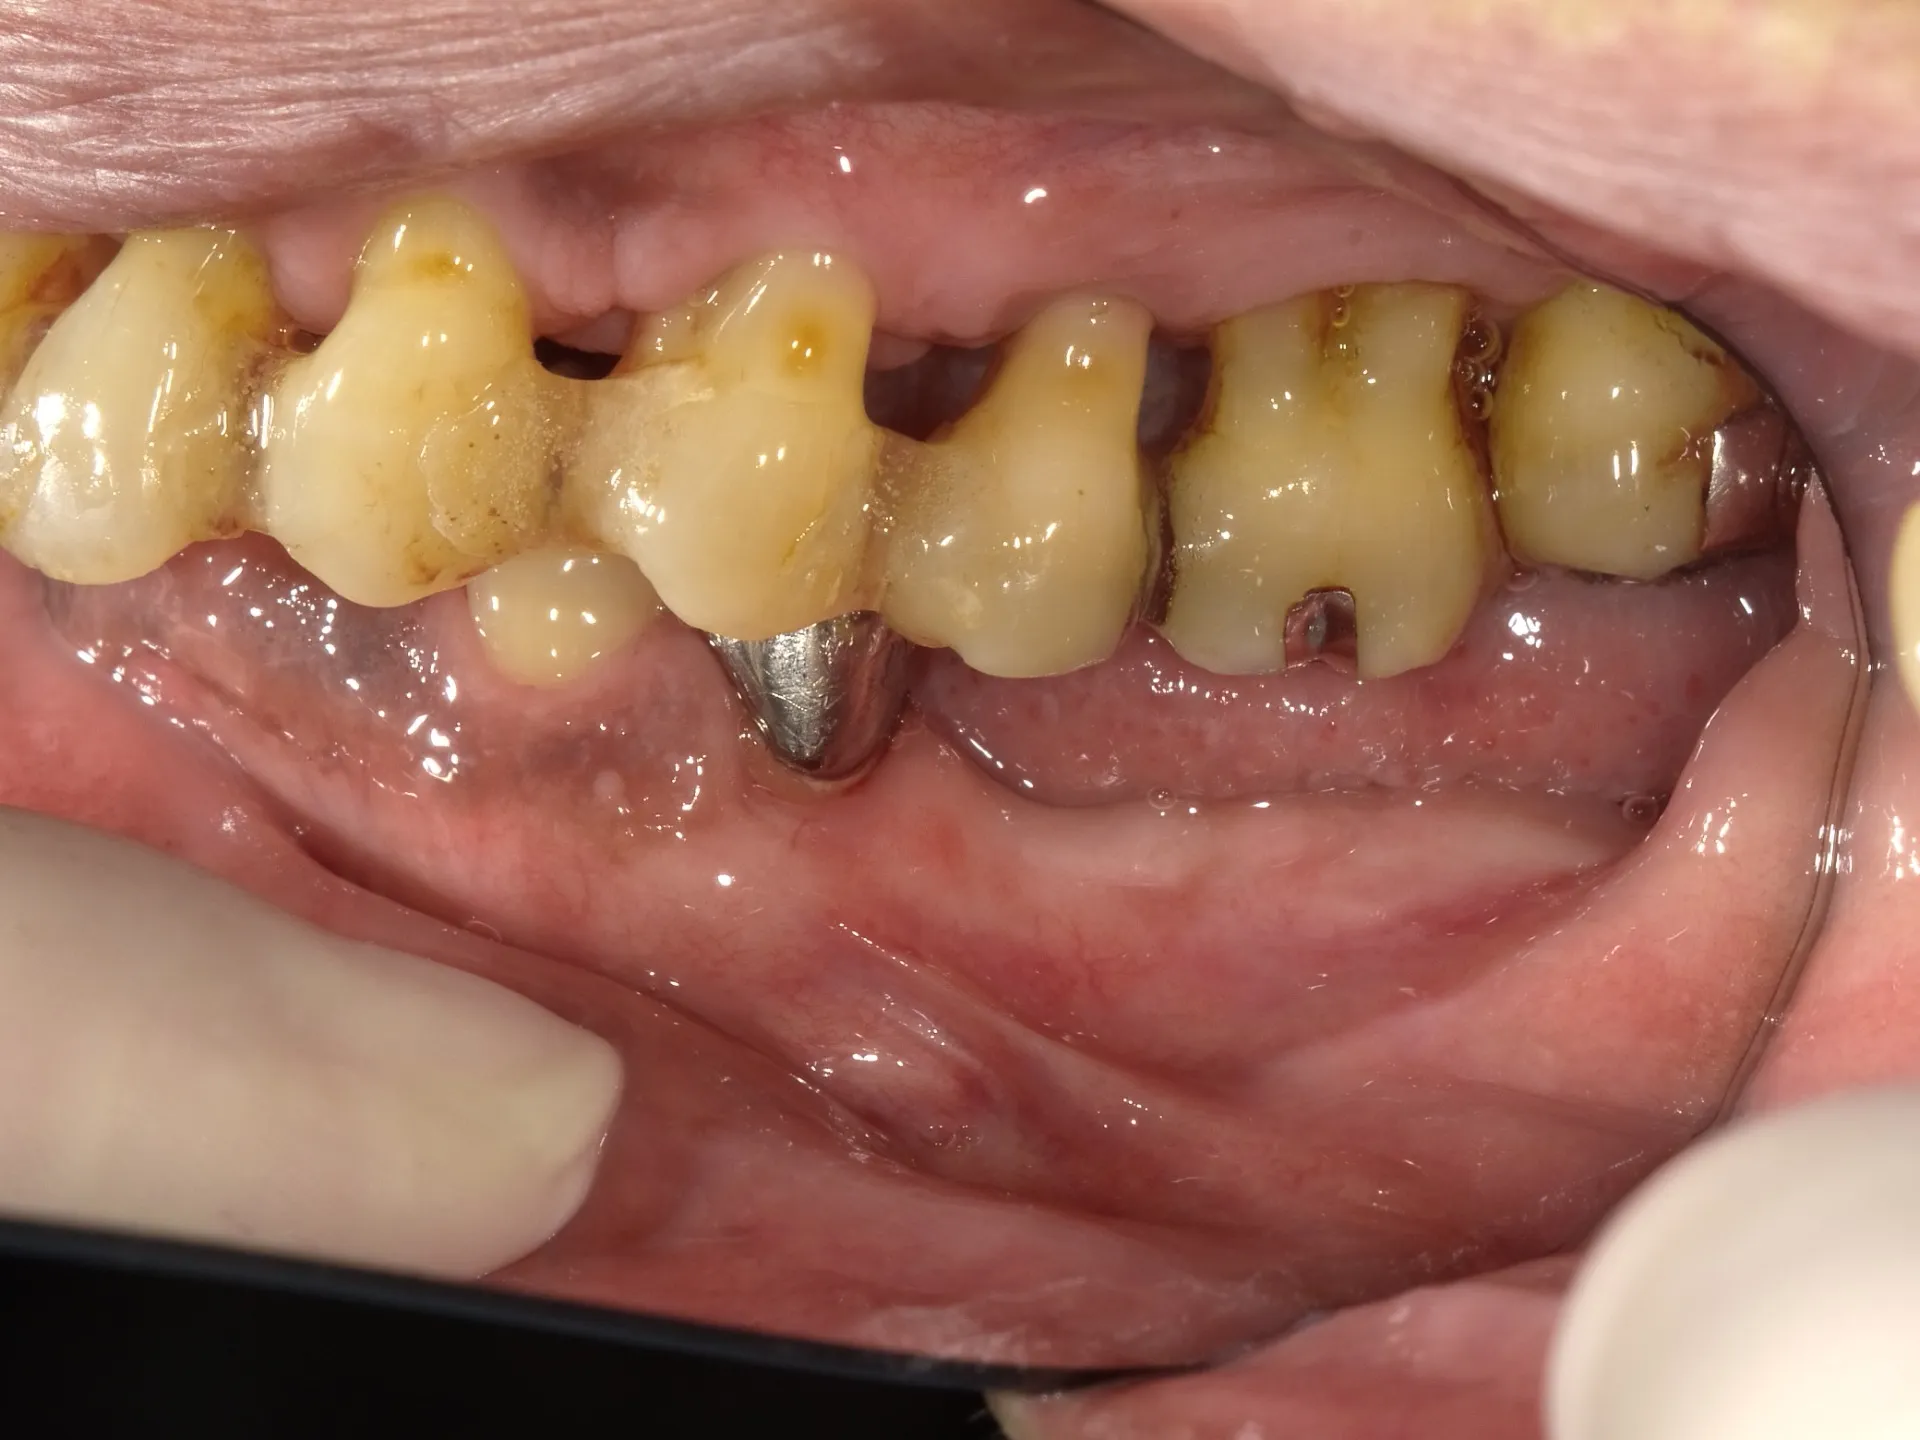

👆SRPを経てBPTSへ移行した状態

20年間、SRPを経てBPTSへ移行しながらメンテナンスを続けてきた方の歯茎。